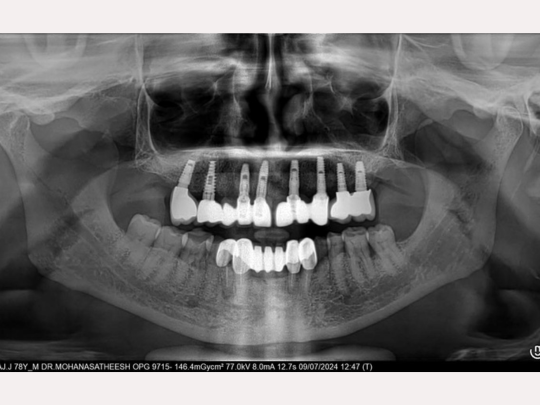

Implant

Before and After